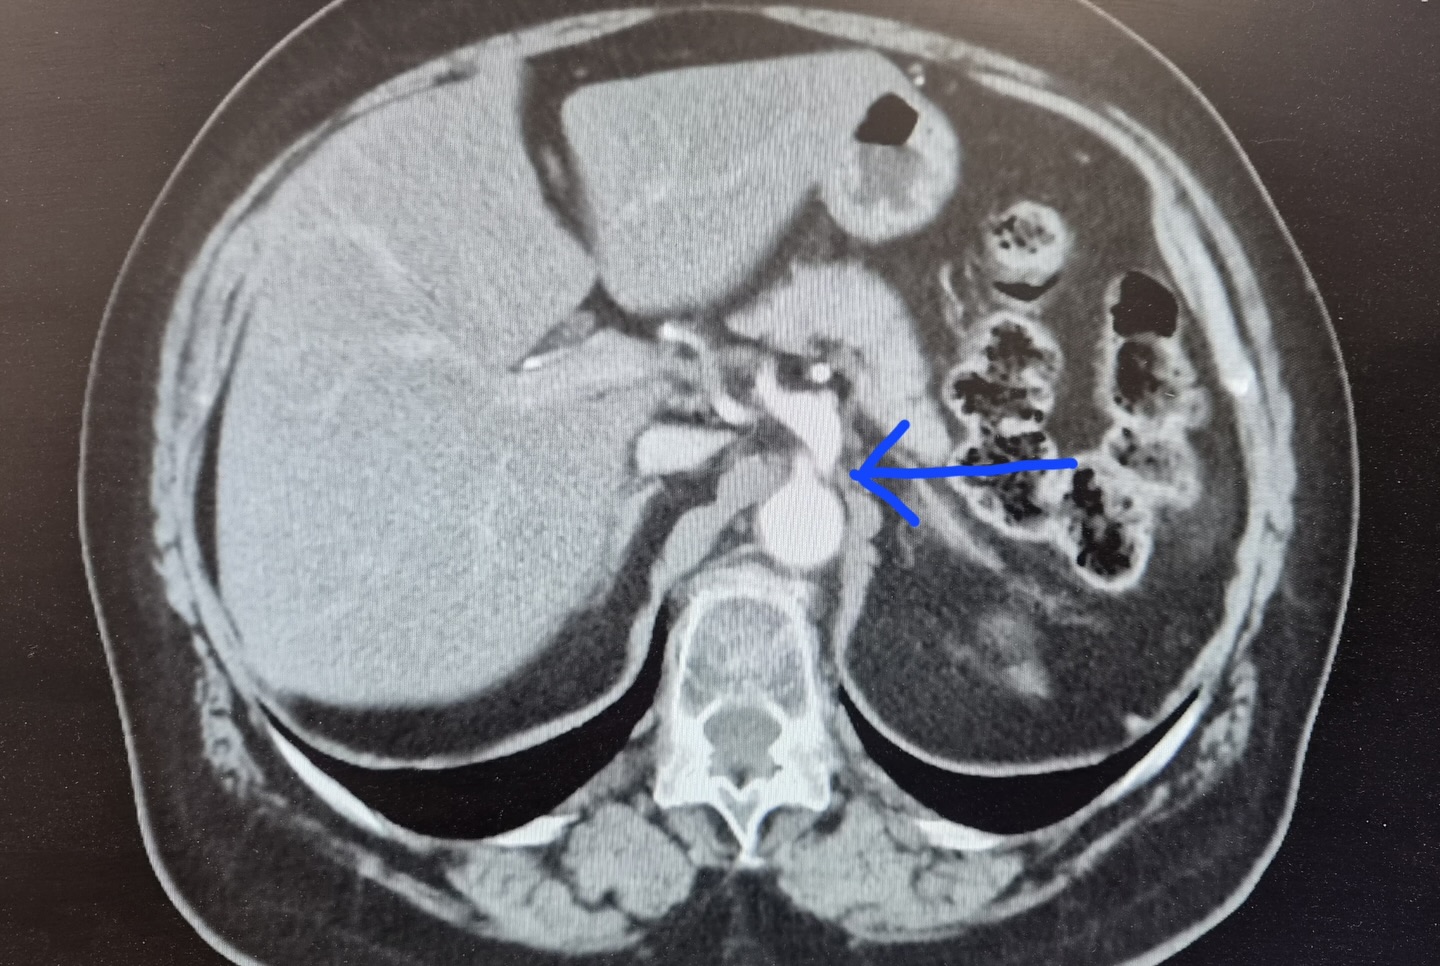

Obraz TK jamy brzusznej: strzałka wskazuje na pień trzewny (truncus coeliacus) czyli krótkie, ale kluczowe naczynie odchodzące od aorty brzusznej, które zaopatruje w krew m.in. wątrobę, żołądek i śledzionę. Zespół Dunbara polega właśnie na ucisku tego naczynia (pnia trzewnego) przez więzadło łukowate przepony, co daje dolegliwości bólowe brzucha, szczególnie po spożyciu posiłków.